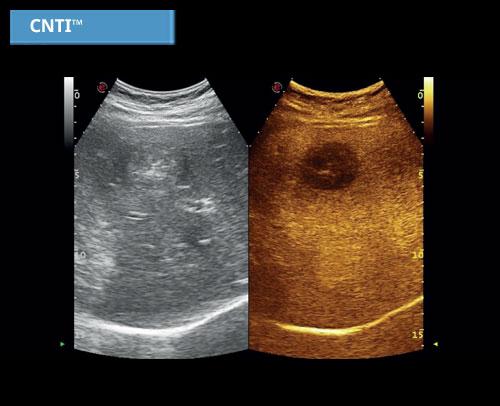

CnTI ™ Contrast Tuned Imaging: Vysoká citlivost, hluboká penetrace a vysoké rozlišení jsou běžné vlastnosti technologie CnTI ™ Contrast Enhanced Imaging pro lepší diagnostický výkon.